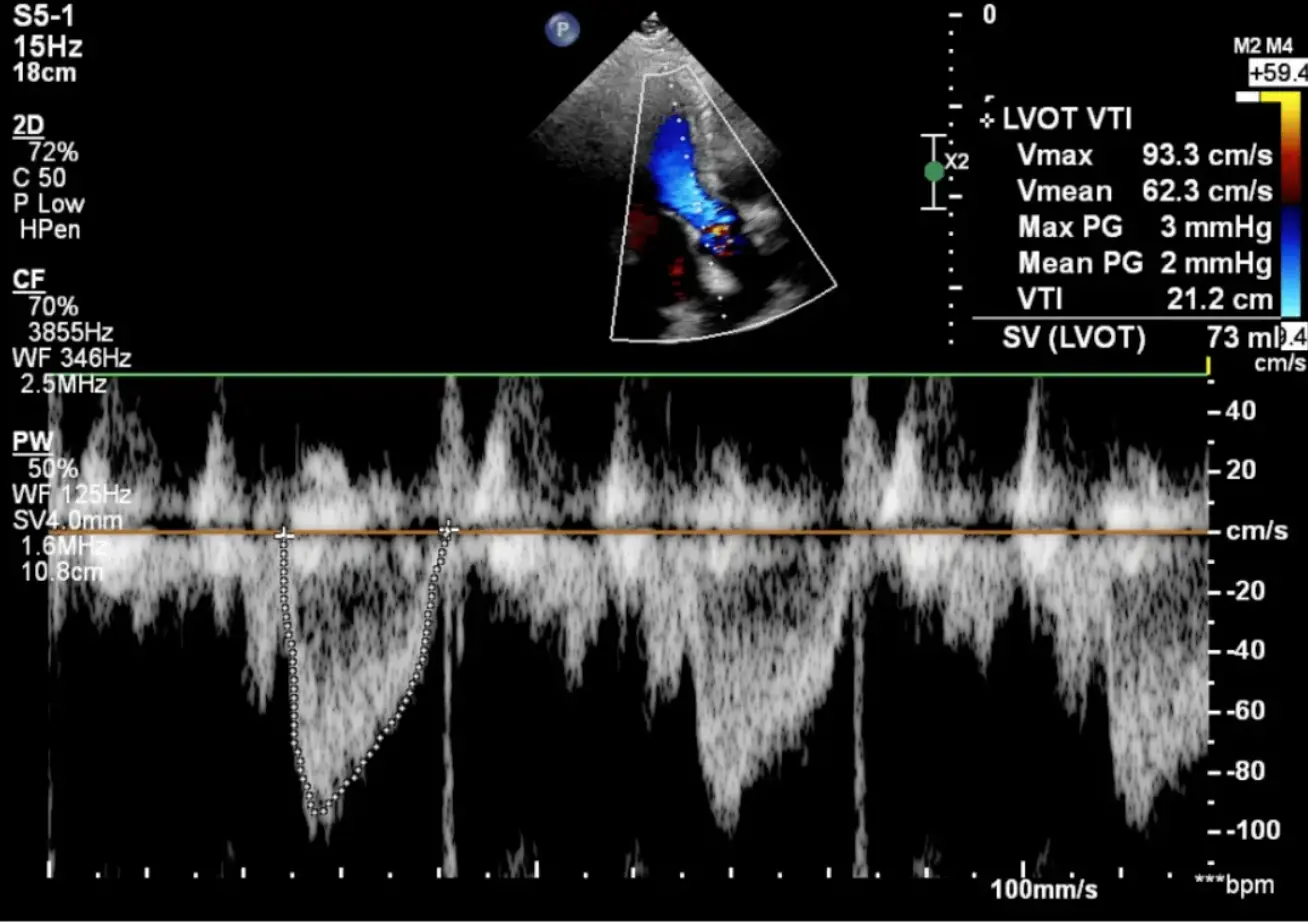

📈 Medida do VTI da VSVE (Doppler Pulsado)

• Janela: Apical 5 câmaras (ou apical 3 câmaras como alternativa)

• Doppler: Posicionar o Doppler Pulsado (PW) no mesmo local onde mediu o diâmetro

• Volume amostra: Posicionar 0.5-1.0 cm proximal (abaixo) da válvula aórtica, dentro da VSVE

• Alinhamento: Alinhar o feixe de Doppler paralelo ao fluxo (ângulo <20°)

• Traçado: Traçar a borda externa (modal velocity) do envelope espectral

• Valores normais: 18 - 22 cm

💡 Dica: Use filtro baixo e ganho otimizado para visualizar bem o envelope. A velocidade máxima normal é <1.0 m/s. Se houver turbulência ou aliasing, reposicione a amostra mais proximalmente.

📊 Média: Em pacientes com arritmia (FA), faça a média de 5-10 batimentos consecutivos para maior acurácia.